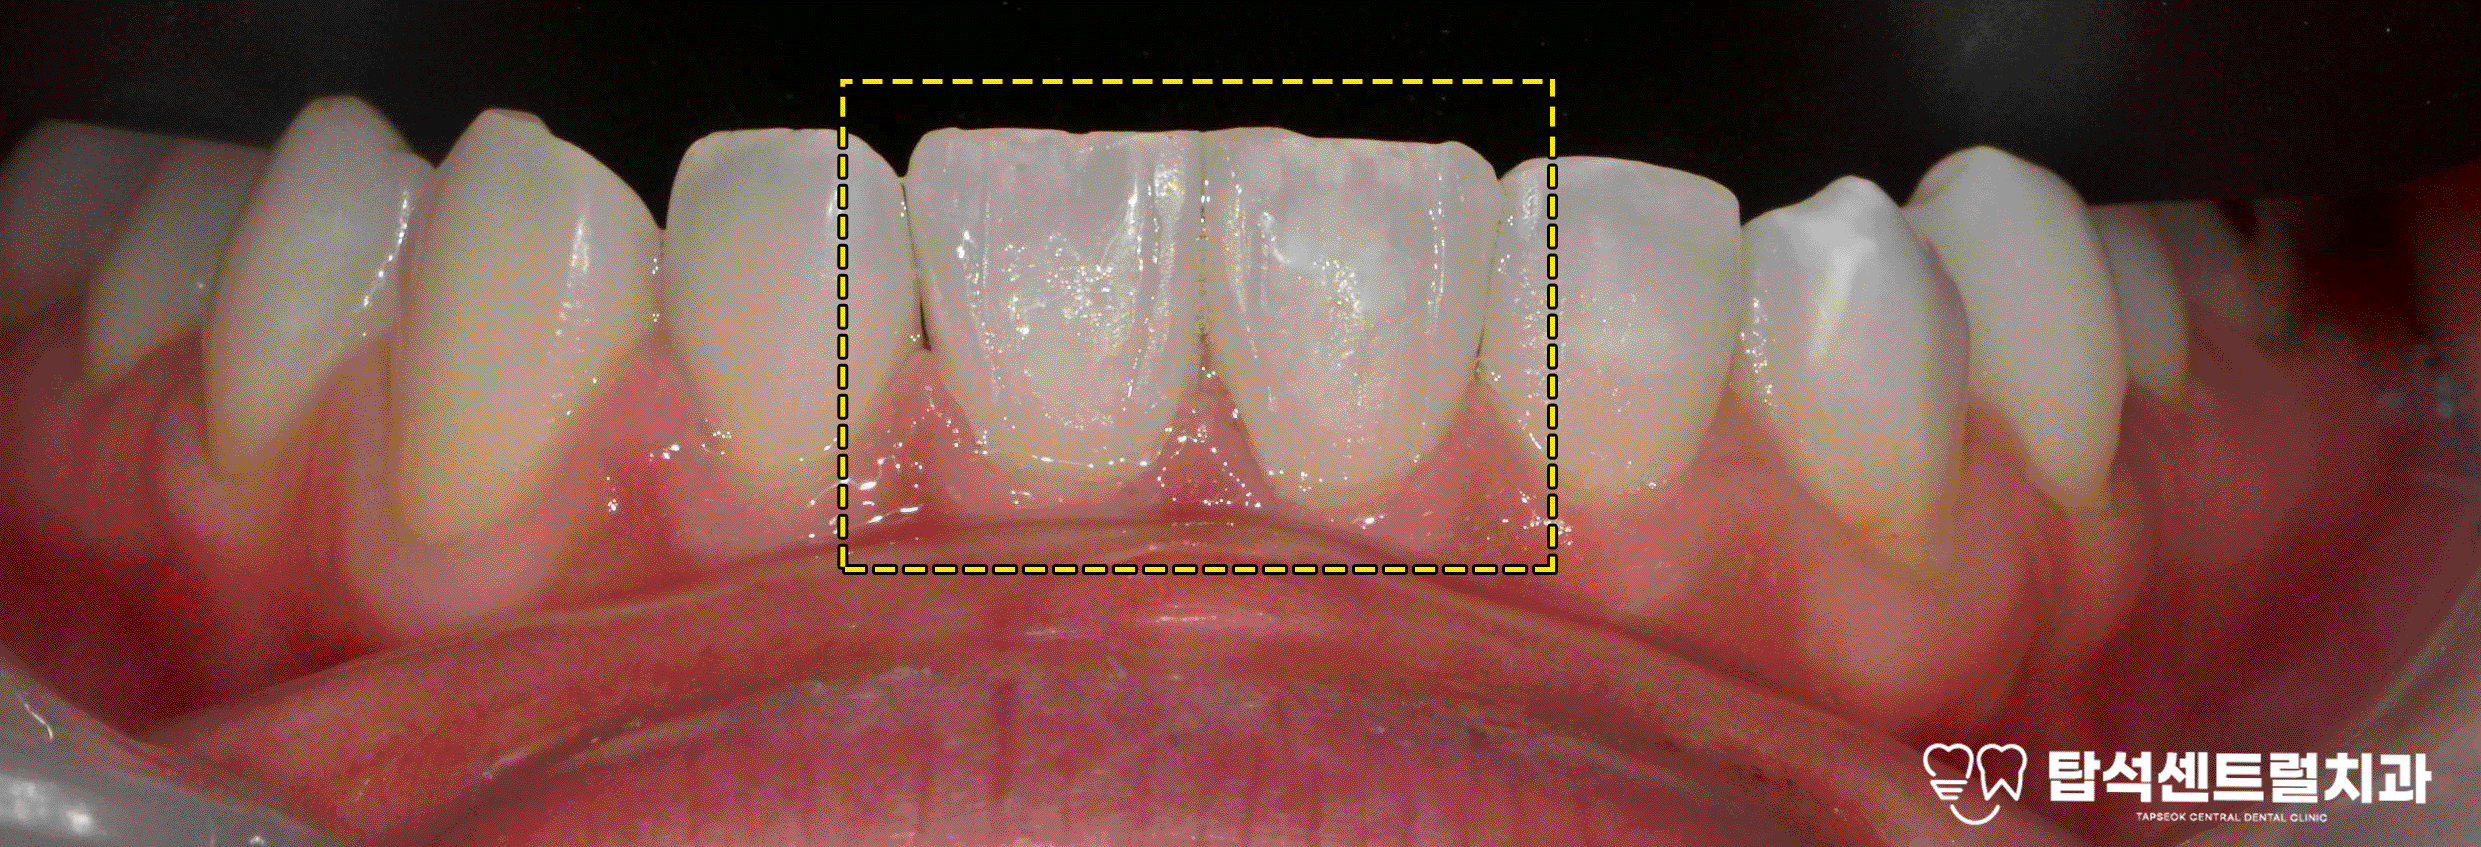

이번 케이스에서는

무삭제 라미네이트 치료를

진행하기로 결정합니다.

민락동 치과 케이스에서는

치료를 시작하기 전

먼저 치아 밝기를 높이는 미백 치료

과정을 진행하기로 결정하게 됩니다.

이후 치아의 안쪽과 바깥쪽

부분에만 적용되는 부분 라미네이트를

제작하여 접착하게 됩니다.

치아 사이 벌어짐 공간이

있는 부위에만 선택적으로 적용하여

자연스러운 결과를 만들어 나갈 수 있습니다.